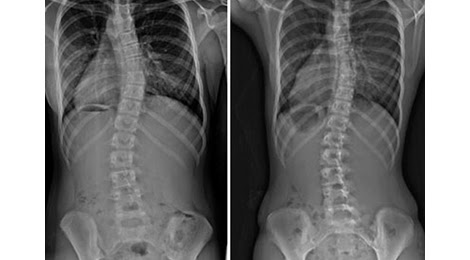

Gù vẹo cột sống: Nguyên nhân và các phương pháp trị liệu hiện nay

Cột sống là một phần quan trọng trong hệ thống xương của cơ thể con người bao gồm một loạt các xương đốt sống được xếp... Đọc tiếp